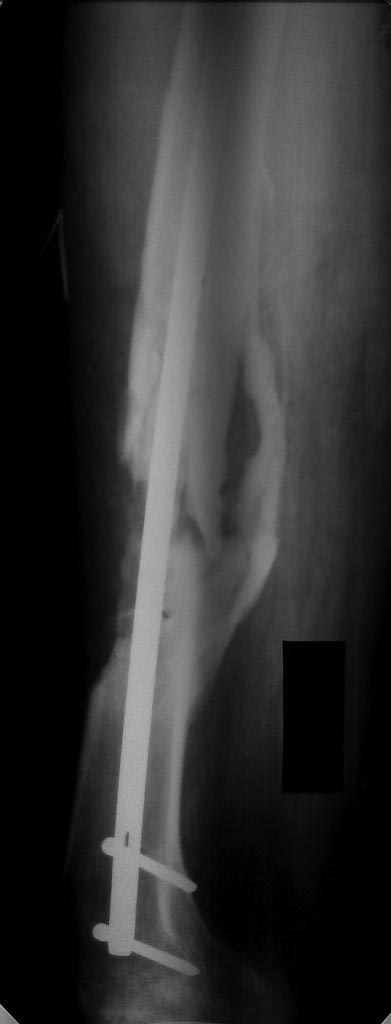

Ничего подобного не замечал особенно на голени.С аппаратом Илизарова мы пережили тяжелое время- девяностые когда кроме спиц ничего не было,заместили кучу дефектов на фоне остеомиелита и все срасталось и не было контрактур особенно в коленном суставе.Нужно просто не нарушать методику проведения спиц.Этот перелом требует не трансплантации ,а адекватной репозиции и жесткой фиксации и не повредила бы ранняя нагрузка на конечность.Посмотрите на снимок-дистальный отломок как будто протянул маленькую ручку к проксимальному-вроде как просит- приблизь его и мы сольемся воедино!

Ситуация немножко напоминает давным-давно тут обсуждавшийся случай - см. тут.

То есть и сейчас вполне уместно заштифтовать в два этапа - то есть сначала исправить аппаратом длину и ось, а пациент пока движения в колене постарается подразработать.

Вообще, можно заштифтовать и одномоментно - аппаратом можно разобщить и вправить отломки сразу, а при стойко неразгибающемся колене штифтовать через артротомию коленного сустава, может, заодно там чего мобилизовать.

Согласен с Андереем Кияночкиным. Вопрос давно решенный: с биологией голени все в порядке, потенциал к сращению не утерян . После этапной постепенной коррекции деформации любой метод СТАБИЛИЗАЦИИ перелома приемлем и функционален: БИОС,АВФ,LCP,DCP.